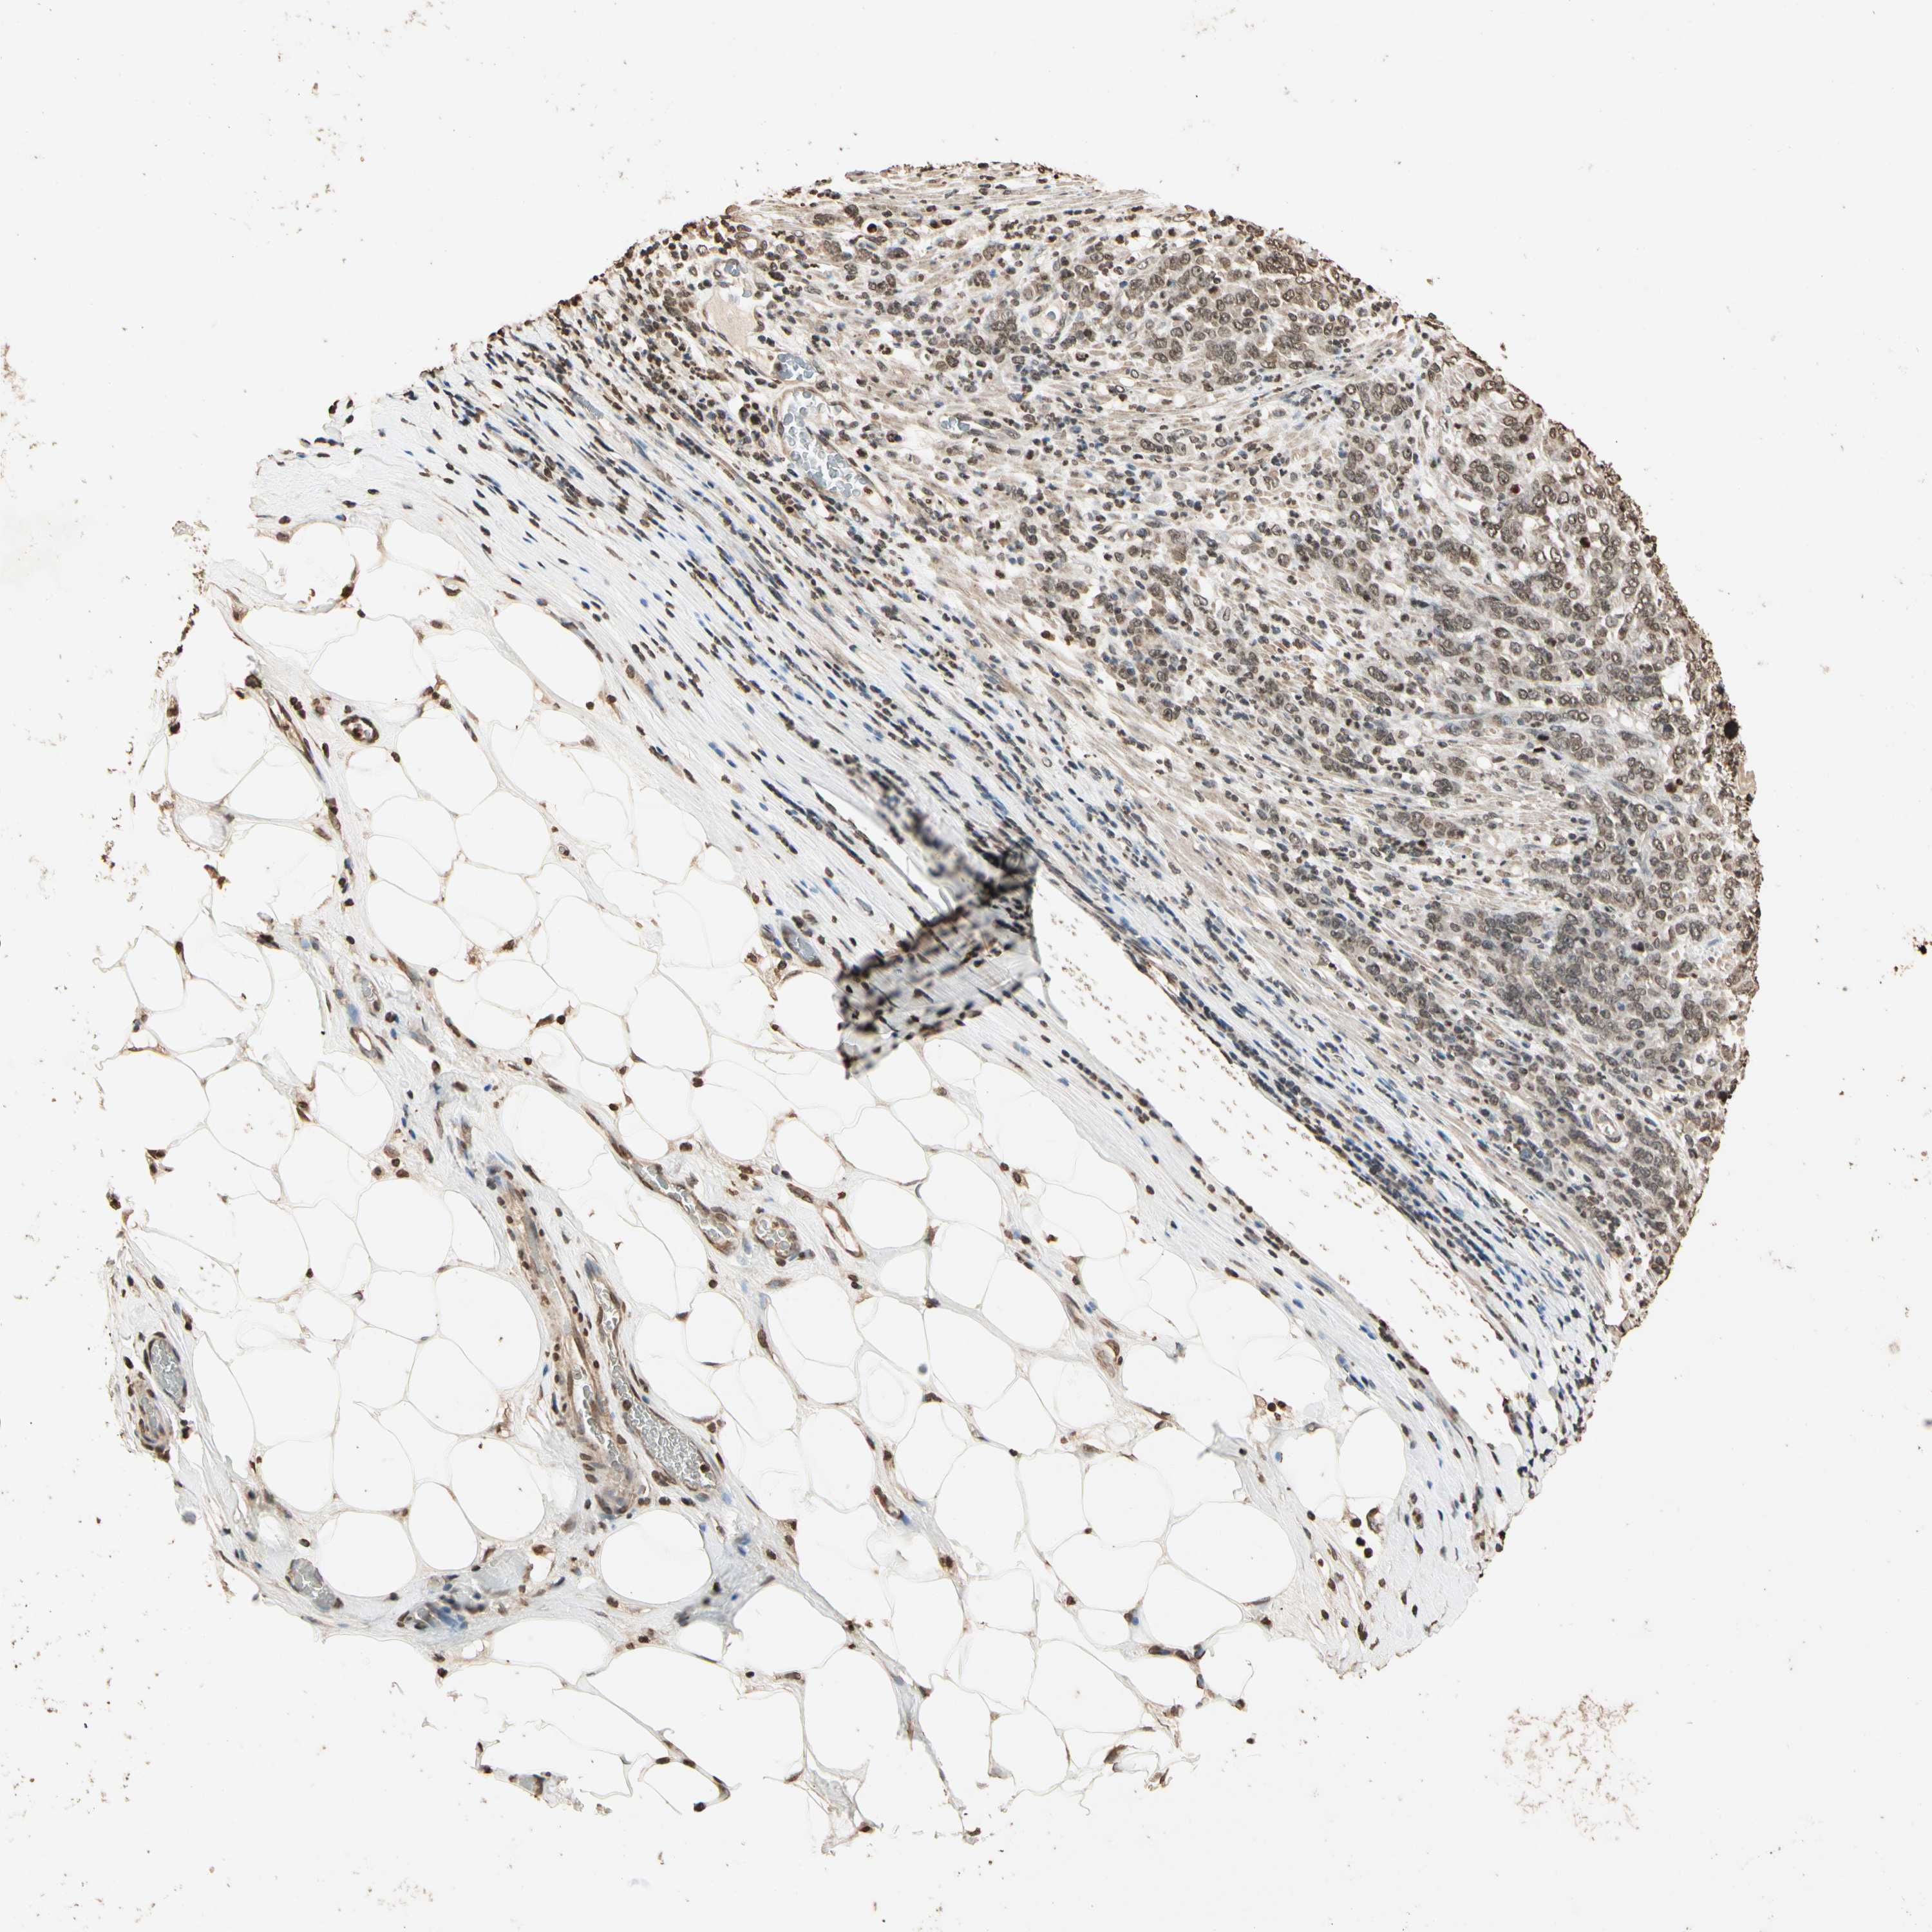

STOMACH CANCER - Protein expressioni

A mouse-over function shows sample information and annotation data. Click on an image to view it in a full screen mode. Samples can be filtered based on level of antibody staining by selecting one or several of the following categories: high, medium, low and not detected. The assay and annotation is described here.

Antibody stainingi

Antibody staining in the annotated cell types in the current human tissue is reported as not detected, low, medium, or high, based on conventional immunohistochemistry profiling in selected tissues. This score is based on the combination of the staining intensity and fraction of stained cells.

Each image is clickable and will lead to virtual microscopy that enables deeper exploration of all samples and also displays staining intensity scores, fraction scores and subcellular localization as well as patient and tissue information for each sample.

Antibody HPA019039

Antibody CAB009058

Staining

High

Medium

Low

Not detected

Intensity

Strong

Moderate

Weak

Negative

Quantity

>75%

75%-25%

<25%

None

Location

Nuclear

Cytoplasmic/membranous

Cytoplasmic/membranous,nuclear

Adenocarcinoma, NOS